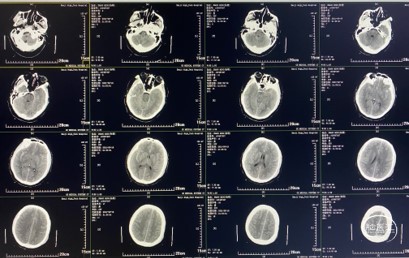

影像学检查

入院时(2021-05-19)头颅CT检查提示:双侧额颞叶点状脑挫裂伤,蛛网膜下腔出血,脑肿胀,侧脑室、三脑室缩小,环池少量积血,中脑轻度受压;